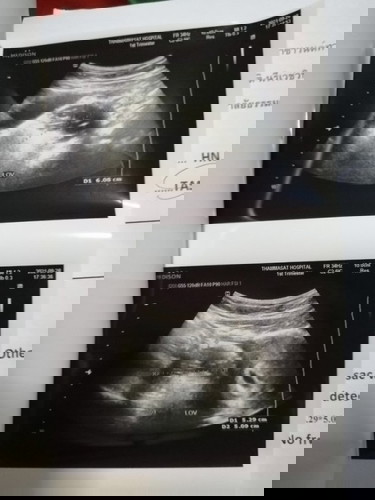

ตอนนี้อายุครรภ์ 12+5W ค่ะ ตั้งแต่ตอนซาวด์ดูน้องครั้งแรก หมอตรวจพบถุงน้ำในรังไข่ฝั่งซ้าย วันที่ 26 ที่ผ่านมาหมอยืนยันผลการตรวจแล้วว่าถุงน้ำเป็นเดอมอยค่ะ (ภายในถุงน้ำจะมีผม กระดูก ฟัน ไขมันอยู่ภายในถุงค่ะ) คุณหมอถามว่าเราจะผ่าตัดหรือเก็บไว้ดี แม่ๆ คิดว่าเราควรทำยังไงดีคะ ถ้าเก็บไว้เสี่ยงบิดขั้ว หรือแตกระหว่างตั้งครรภ์ มดลูกที่โตขึ้นอาจจะไปเบียดถุงน้ำจนแตกได้ ถ้าแตกเราต้องผ่าตัดฉุกเฉิน การผ่าตัดในขณะที่ท้องโตแล้วทำให้ยากในการผ่าตัดค่ะ หรืออีกกรณีถุงน้ำอาจจะเบียดมดลูก ทำให้คลอดก่อนกำหนดได้ ถ้าดีที่สุดคือ ระหว่างตั้งครรภ์ไม่มีปัญหาอะไรเลย รอผ่าตัดออกพร้อมกันตอนผ่าคลอดน้อง แต่ถ้าผ่าตัดก็ต้องผ่าตอนอายุครรภ์ 14-16W ความเสี่ยงคือ เสี่ยงแท้งค่ะ หมอต้องรีบทำการผ่าตัดโดยการตัดรังไข่ฝั่งซ้ายไปเลยค่ะ #ขอคำแนะนำหน่อยค่ะ #ท้องแรกคะ #ขอบคุณล่วงหน้านะคะ #ใครมีประสบการณ์